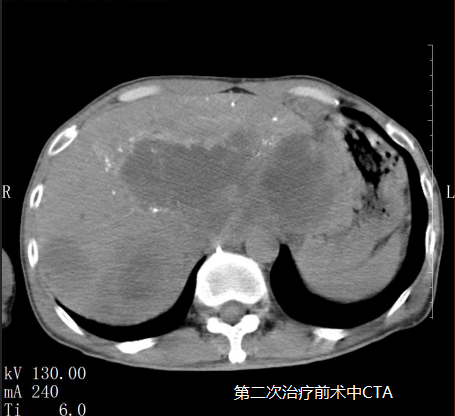

蘇先生進行第二次微血管介入治療后明顯感受自己的身體變得輕盈,可以進行簡單的飲食,精神狀態(tài)變好了。

在5月3日蘇先生的肝指標檢查中甲胎蛋白降為6671IU/ml(參考值0~5.8),隨后王峰醫(yī)生實時跟進蘇先生病情為他制定后續(xù)的治療方案,為他開對應的藥物治療;5月14日蘇先生的肝指標檢查中甲胎蛋白降為18.70U/ml(參考值0~5.8)。

5月18日是蘇先生進行第三次微血管介入治療,治療后蘇先生完全可以自理,飲食恢復正常,面色也慢慢紅潤起來,腫瘤從原來的16公分縮小至10公分,甲胎蛋白逐漸趨向正常,看到這樣的結果也讓醫(yī)生們深感很欣慰,連蘇先生也意想不到,前段時間自己還是生命瀕危的癌癥患者現(xiàn)在卻可以像正常人一樣生活。他覺得這是上天給他最大的驚喜。